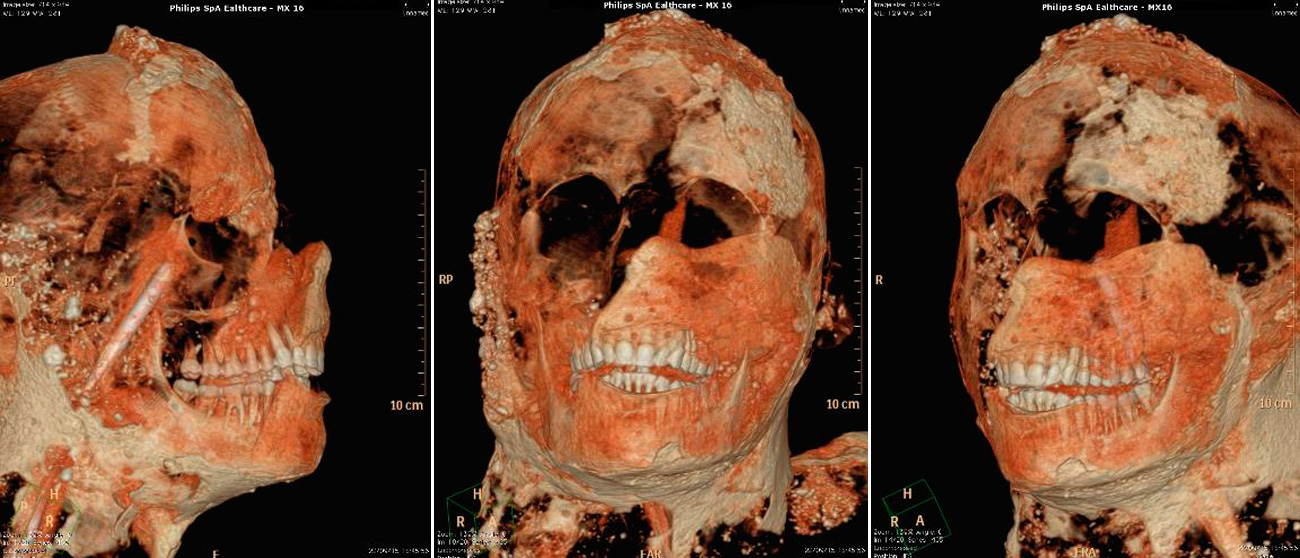

Entre las conclusiones de la investigación figura la evidencia de que tenían dientes en buen estado gracias a una buena alimentación basada en pocos azúcares, así como que se servían de la dentadura para romper y cortar alimentos y útiles relacionados con las actividades cotidianas o artesanales.

“Los dientes puden aportar información sobre los hábitos de vida de una persona, además de sobre sus ocupaciones”, cuentan los responsables de la investigación, que añaden que también averiguar si era flautista o fumador de pipa, por ejemplo, así como su origen geográfico y sus condiciones socioeconómicas”.

Asimismo, han sido realizados relieves en tres dimensiones de todos los cuerpos mediante técnicas digitales de vanguardia que permiten obtener datos sobre cómo ha variado su estado de conservación en el tiempo.